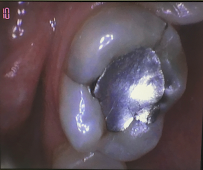

• Restorative Dentistry – dental crowns, bridges, fillings, and tooth restoration to repair damaged or decayed teeth